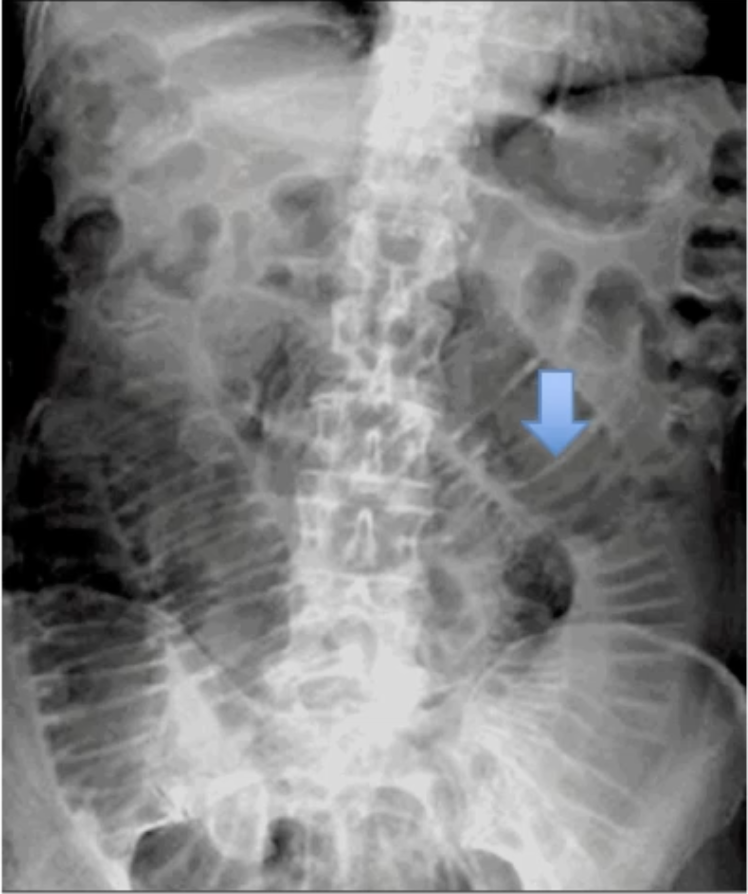

What does this AXR show?

Valvulae Conniventes

Small Bowel Dilatation (Obstruction)